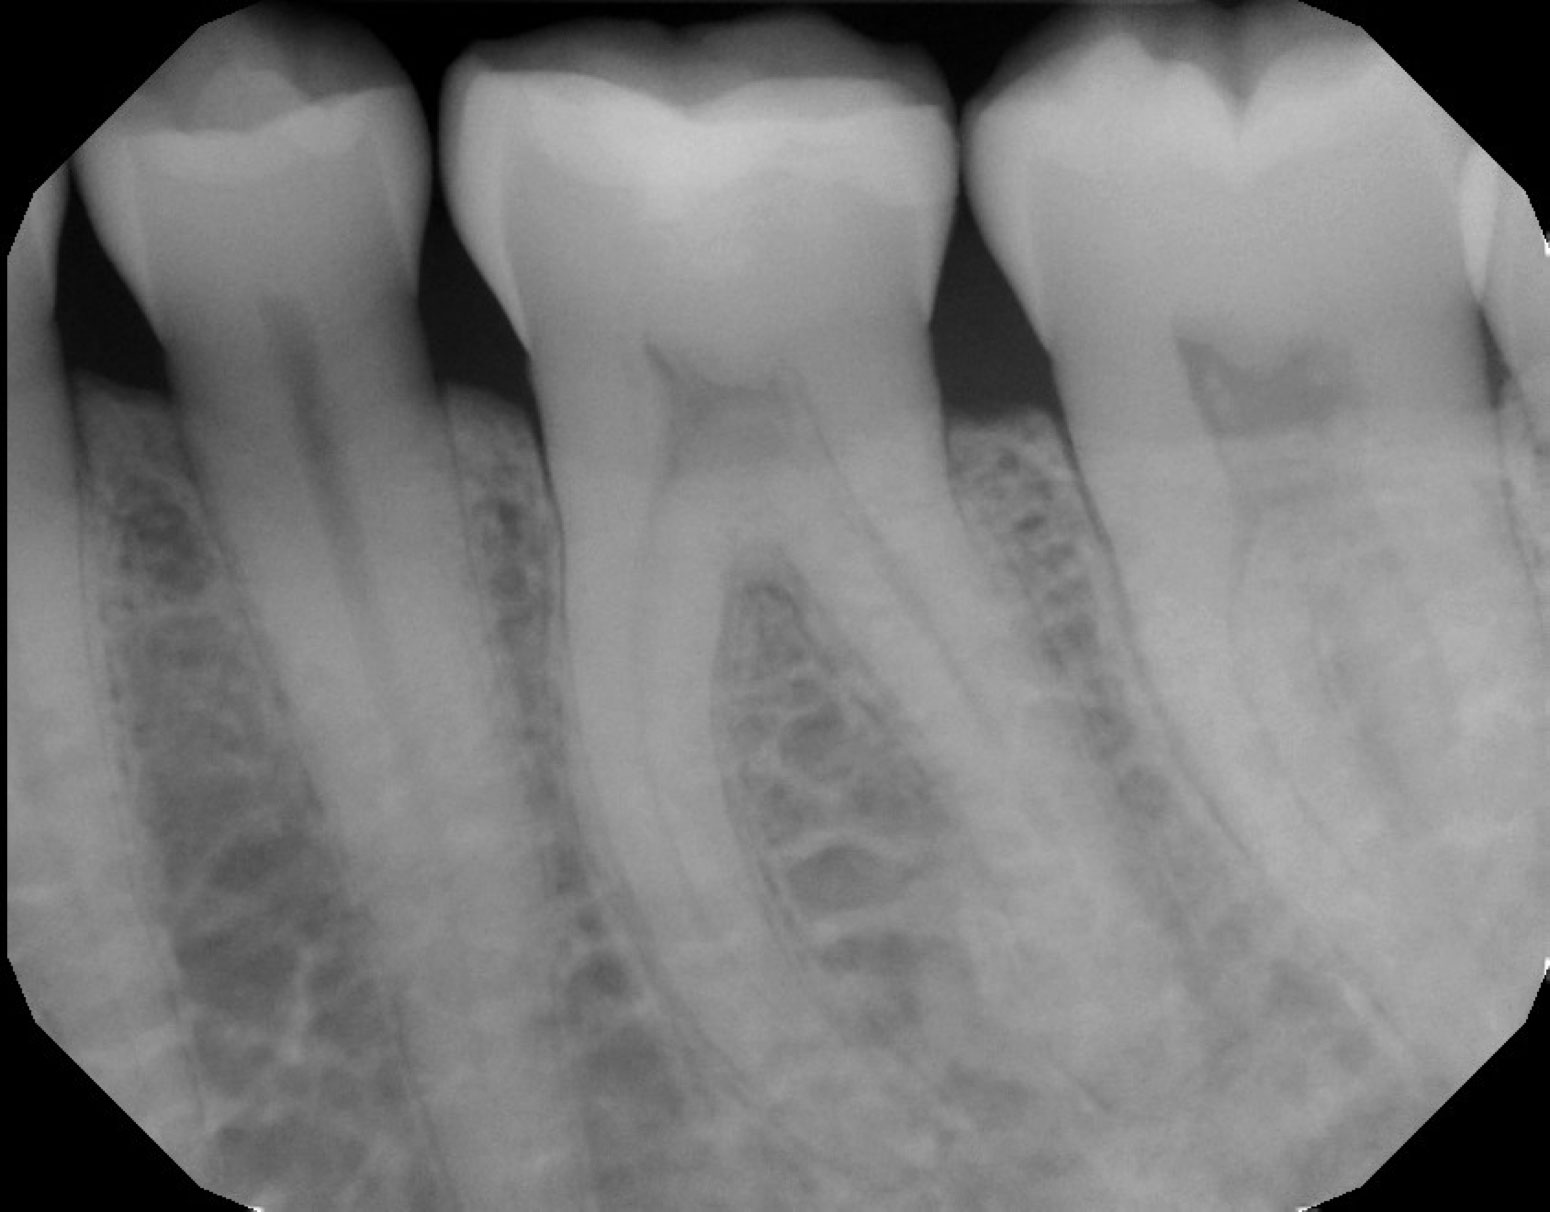

Endodontics is a specialty of Dentistry that deals with diseases of the dental pulp and its supporting structures. The treatment preserves your natural tooth, usually in a single appointment, and avoids an extraction or implant.

At our clinic, we use advanced imaging, microscope operating techniques, combined with our years of specialist training to diagnose and treat complex cases – all in a calm and supportive environment.

Although all dentists are able to carry out some simpler endodontic treatments, a further period of study, 2-3 years after graduation enables a select number of dentists to qualify as a registered endodontic specialist. It is well recognised within the profession and literature that success rates in terms of tooth survival and elimination of infection are much greater when the treatment is completed by an endodontist.